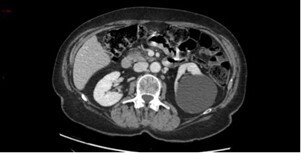

Le scanner ci-dessous est réalisé.

Question 3 - Dans les coupes précédentes, quelles sont les structures désignées par les flèches ?

Veine cave inférieure.

Corps vertébral.

Voies veineuses de dérivation péri-gastriques.

Question 4 - Vous constatez (une ou plusieurs réponses exactes) :

Non pas du foie gauche (= lobe gauche + segment IV) mais du lobe gauche (segments II et III).

Flèche verte.

La dysmorphie hépatique est caractérisée par une hypertrophie de segment I (en arrière du tronc porte et en avant de la veine cave inférieure) et du lobe gauche (segments II et III situés à gauche de la veine hépatique gauche) ; ainsi que par une hypotrophie du segment IV (situé entre les veines hépatiques gauche et médiane, séparé du lobe gauche par le plan passant par la veine hépatique gauche et le ligament rond). Peut également s’y associer une hypotrophie du secteur postérieur du lobe droit (segments VI et VII).

Pour la segmentation hépatique, voir la figure ci-dessous : On retrouve comme autre signe d’hépatopathie chronique les contours bosselés.

Les signes d’hypertension portale visibles en scanner sont :

– les voies veineuses de dérivation porto-systémiques (spléno-rénales, gastro-rénales, mésentériques, rétro-péritonéales…) ;

– la splénomégalie.

L’analyse des coupes abdominales montre également les images suivantes :